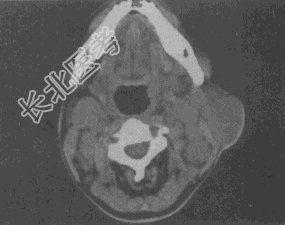

- 单项选择题女,25岁, 发现双侧颈部肿块近10年,CT如图, 最可能的诊断为

A、巨淋巴结增生症

B、淋巴瘤

C、转移瘤

D、淋巴结结核

E、淋巴结炎